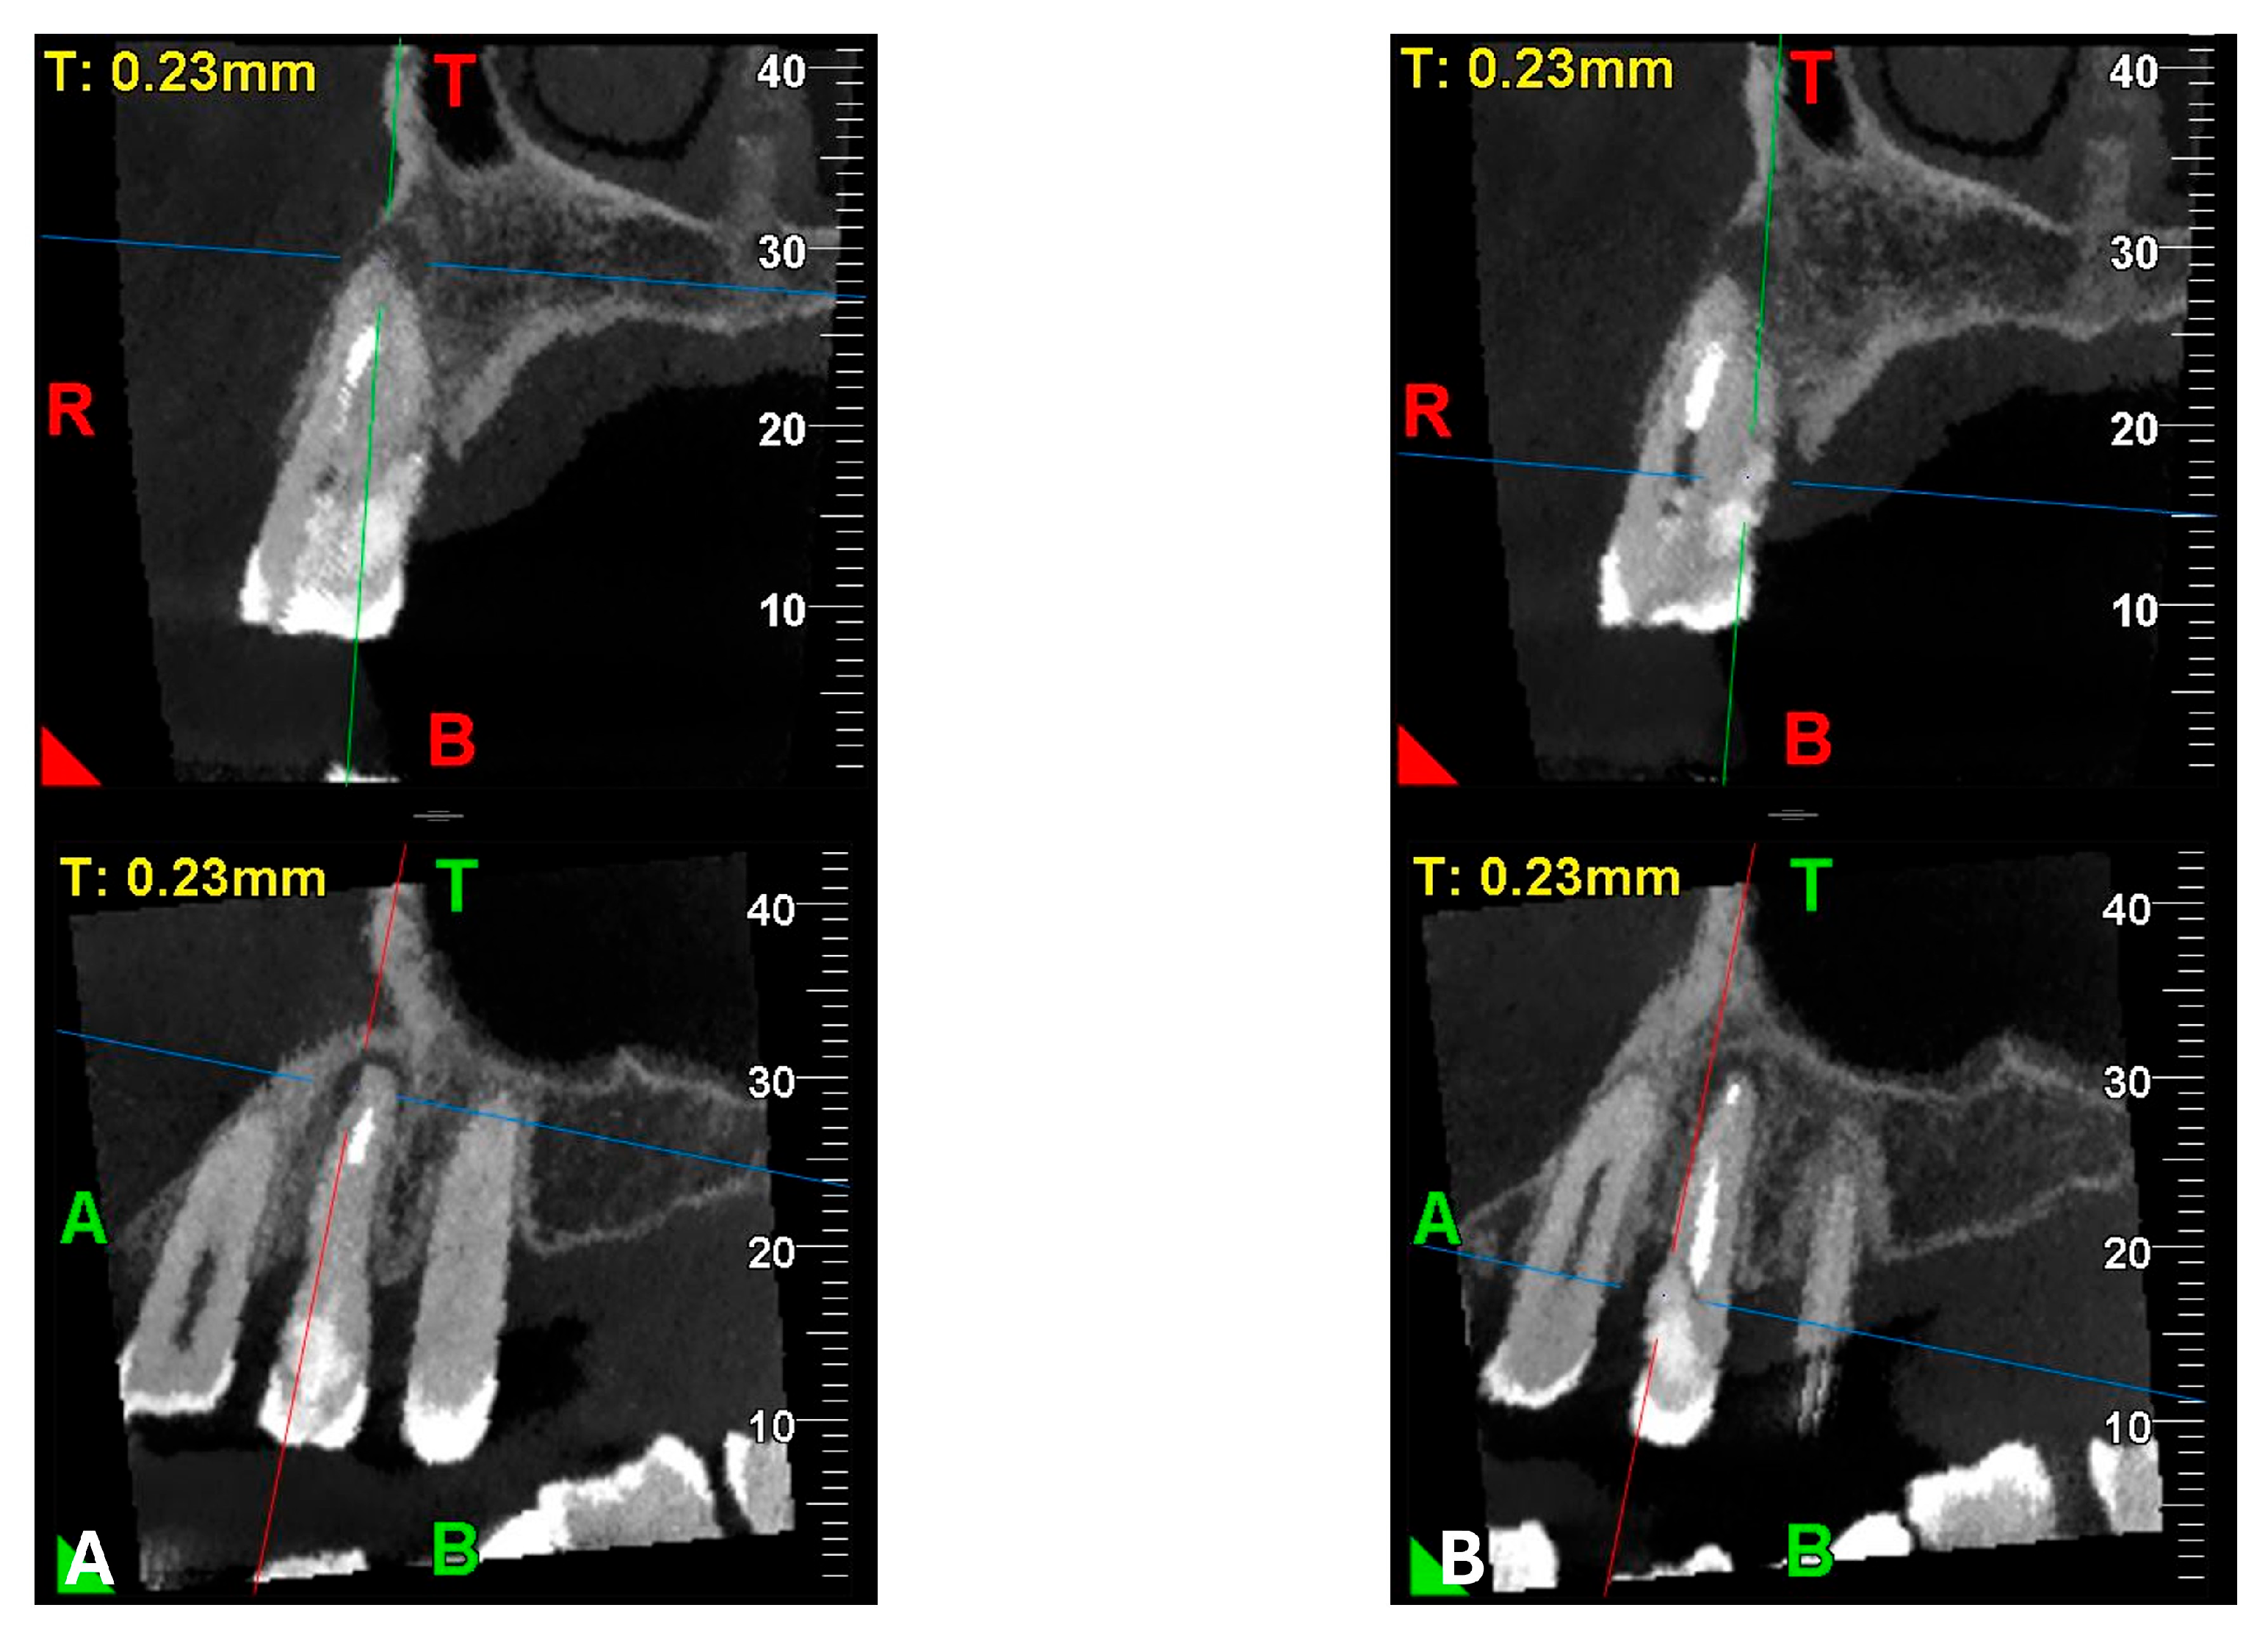

A CBCT examination (X9 Pro®, MyRay, Imola, Italy), performed with dedicated field of view (FOV) (6 × 6) and exposure parameters, was essential for accurate diagnosis and treatment planning. This device optionally features a specific Booster function for users with advanced expertise, which allows for further customization of exposure parameters to optimize the examination more effectively. Optimal management of the FOV, properly centered and limited to the anatomical area of interest, in this specific case slightly extended (6 × 6) to clearly rule out a possible involvement of the maxillary sinus in agreement with the attending otorhinolaryngologist, enabled the acquisition of broader and more detailed clinical and diagnostic information, which is essential in endodontics. Moreover, it allowed for a significant reduction in radiation dose while optimizing spatial resolution [22]. The imaging clarified the extent of the resorption and defined its perimeter, demonstrating an endodontic-periodontal communication, classified as 3Bp according to Patel’s classification [21] (Figure 2, Figure 3, Figure 4 and Figure 5).

Figure 4.

Pano-rex and cross-sectional CBCT images of tooth 1.4, showing its ECR, EPL, and PL. The colored lines crossing the images represent the orthogonal planes (axial, coronal, and sagittal) in the multiplanar reconstruction. Their correct use and orientation allow for an accurate identification of the extent of the lesions, including possible relationships with the maxillary sinus, in all spatial planes and a detailed analysis of the endodontic anatomy. The green and red letters are the coordinates of the image: A: anterior, R: right, B: bottom, T: Top.

An intermediate follow-up CBCT scan at 6 months was performed to accurately assess the response to treatment in light of both the extent of the lesion and the patient’s systemic comorbidities (Figure 10, Figure 11, Figure 12, Figure 13 and Figure 14).

Figure 12.

Pano-rex and cross-sectional CBCT images of tooth 1.4 after six months of healing. (A,B) Sequential scrolling of tooth 1.4 after six months of healing. The colored lines crossing the images represent the orthogonal planes (axial, coronal, and sagittal) in the multiplanar reconstruction. Their correct use and orientation allow for an accurate identification of the extent of the lesions in all spatial planes and a detailed analysis of the endodontic anatomy. The green and red letters are the coordinates of the image: A: anterior, R: right, B: bottom, T: Top.